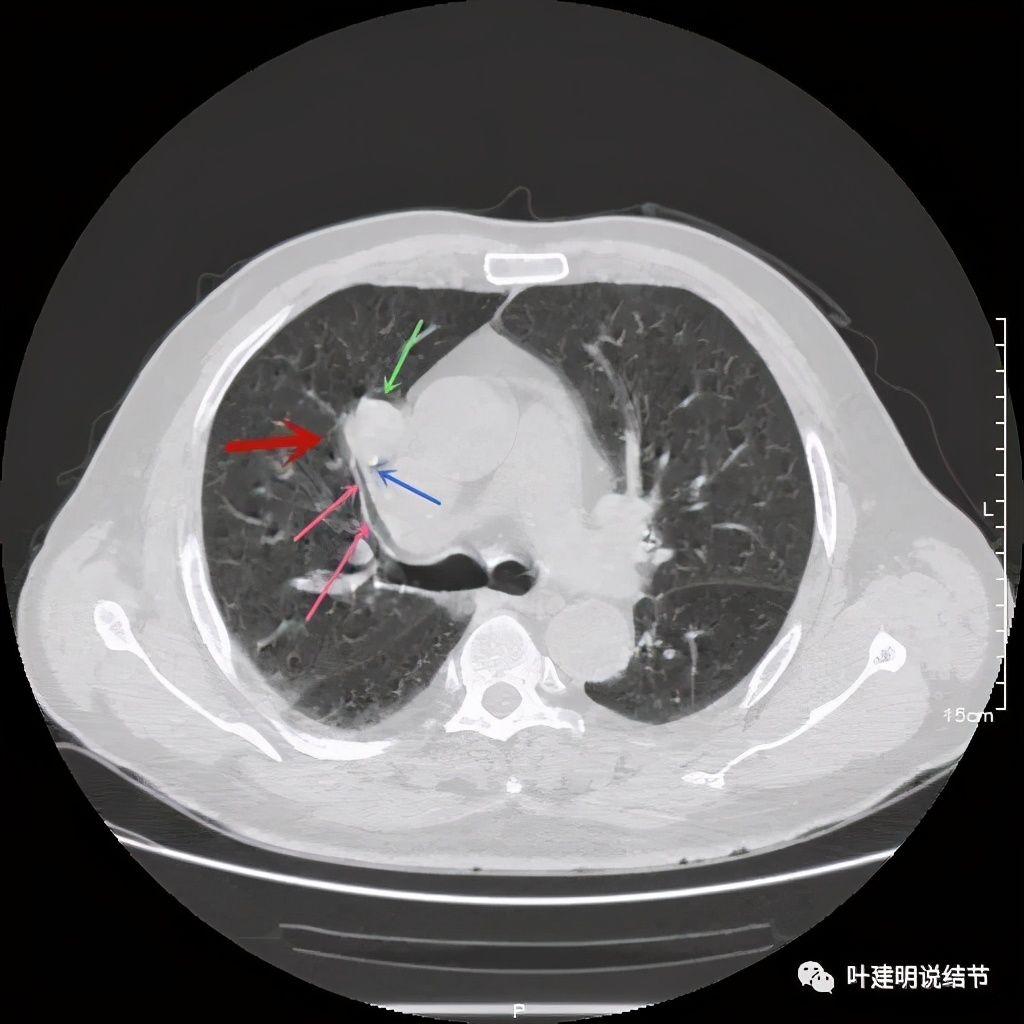

可见右上叶占位,我们现在知道了结果以后回头看,发现病灶的边缘在各个层面都是过于光滑(绿色箭头所示)。血管紧贴病灶边走行(桔色箭头所指),是不是有侵犯看不清楚,若是靶扫描加重建可能会更清楚点。支气管感觉也是贴着病灶走,但有的层面是不是截断,也不看的不太清楚。有的层面见局部有点状高密度(蓝色箭头所指),是不是错构瘤的局部钙化呢?若是纵隔窗又是如何?

上图示病灶

上图示病灶密度不均

上图示病灶局部点状高密度(蓝色);边缘过于光滑(绿色)

上图示病灶密度不均,但边缘过于光滑(绿色);支气管似有截断(粉色);局部有点状钙化(蓝色)